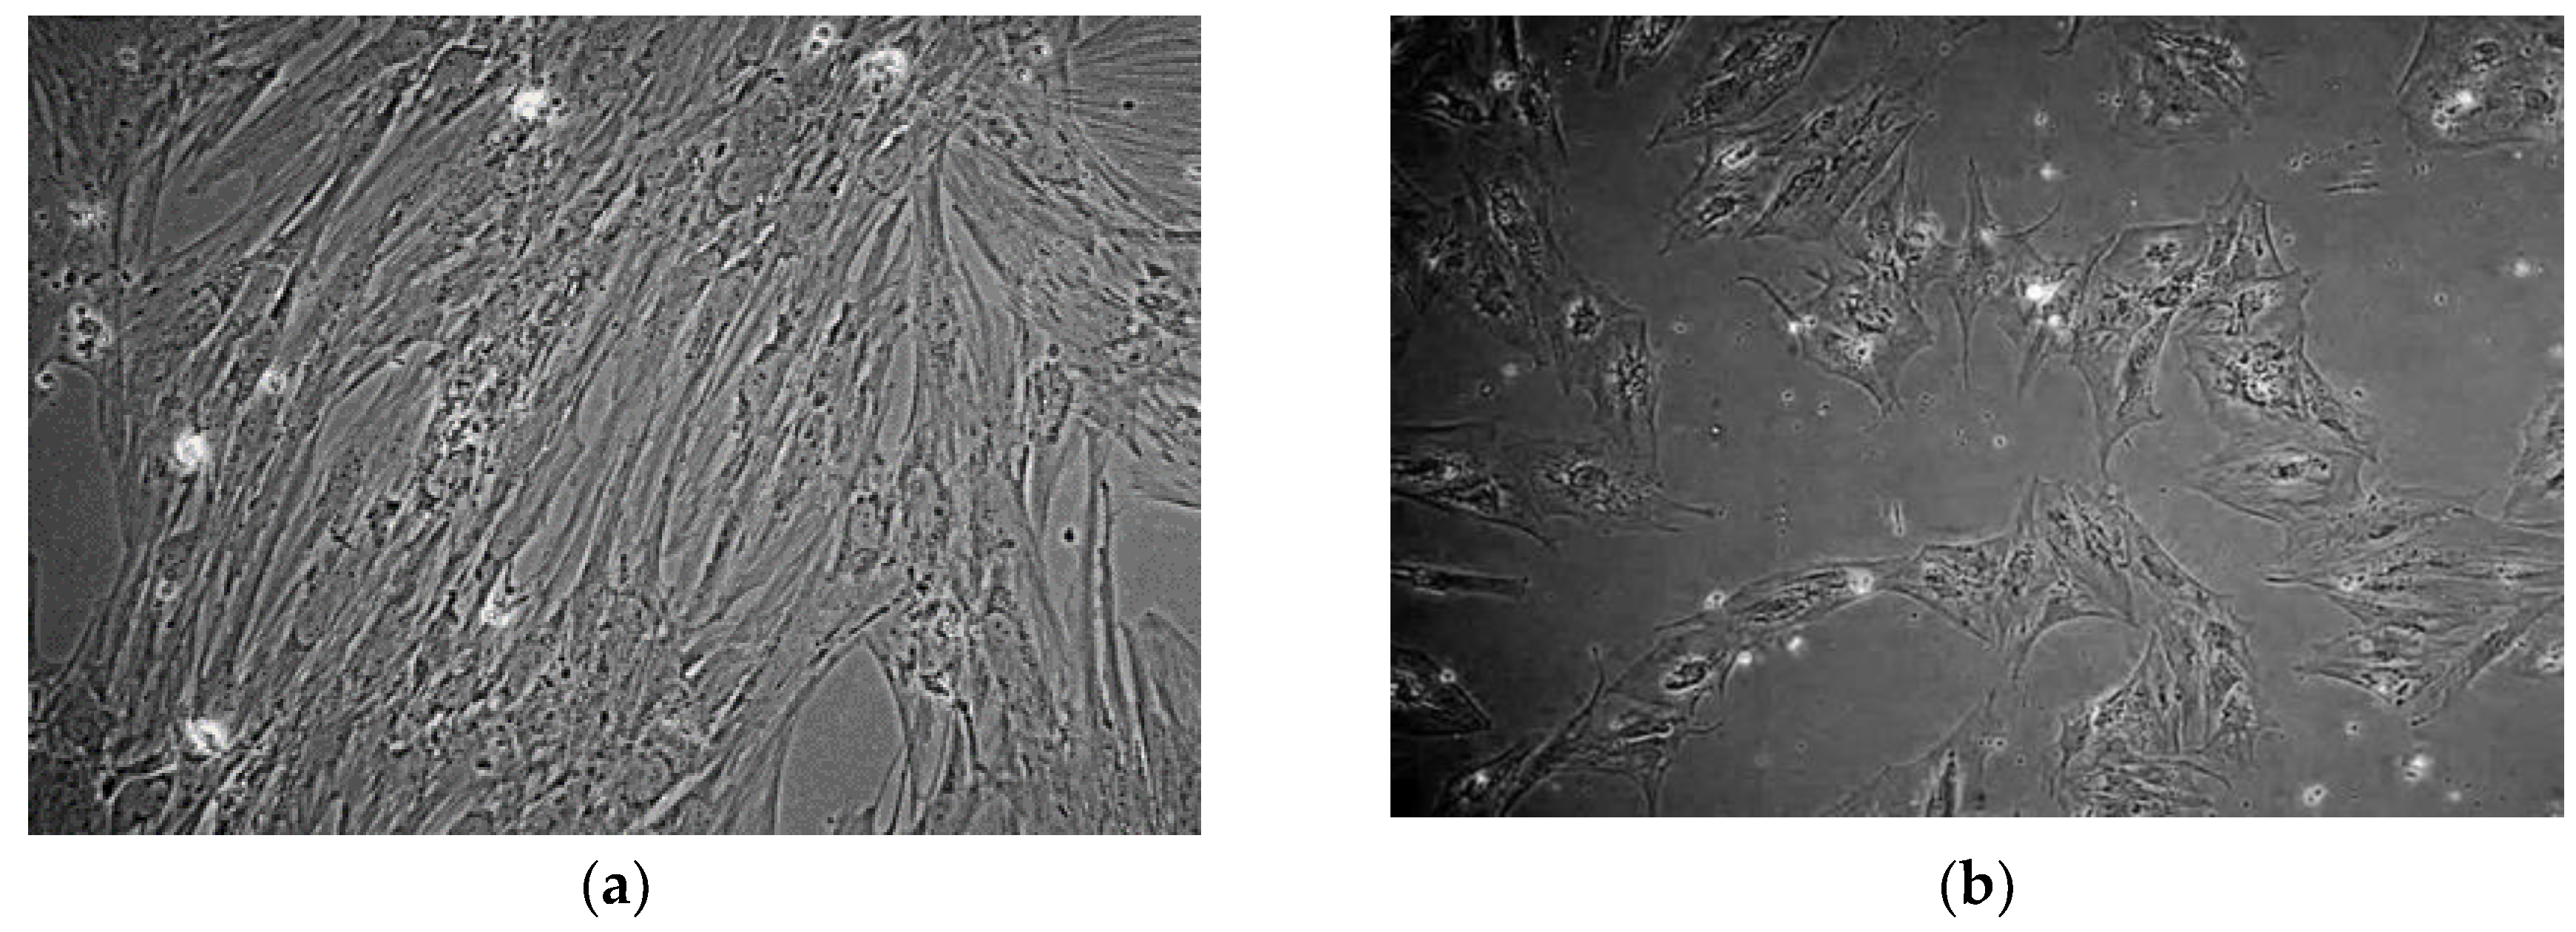

The patient derived cell populations were also imaged on a regular basis to document their growth rate and monitor for unexpected morphological changes. We found that the average in-vitro doubling time of BM001 was 36 h, of BM002 was 120 h, and of BM004 was 23 h. Figure 1 (a and b) show images taken at weeks 1 and 3 of the hBM-MSCs bi-dimensional expansion, respectively [15].

Figure 1. Inverted light microscope images of human bone marrow mesenchymal stem cells (hBM-MSC). (a) hBM-MSCs cultured from subject BM004 that were grown in 2D culture at 1 week post-harvest (100× magnification); (b) hBM-MSCs cultured from subject BM004 that were grown in 2D culture at 3 weeks post-harvest (100× magnification).